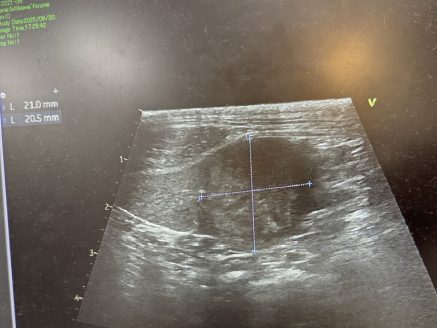

「下痢や嘔吐を繰り返したため9月30日に精密検査を行ったところ、脾臓や腹腔内に腫瘍が見つかりました。

皆さまからのご寄付は、この検査費および治療費として活用させていただきました。現在はかかりつけ医と相談しながら、手術に向けて体調を整えている段階です」